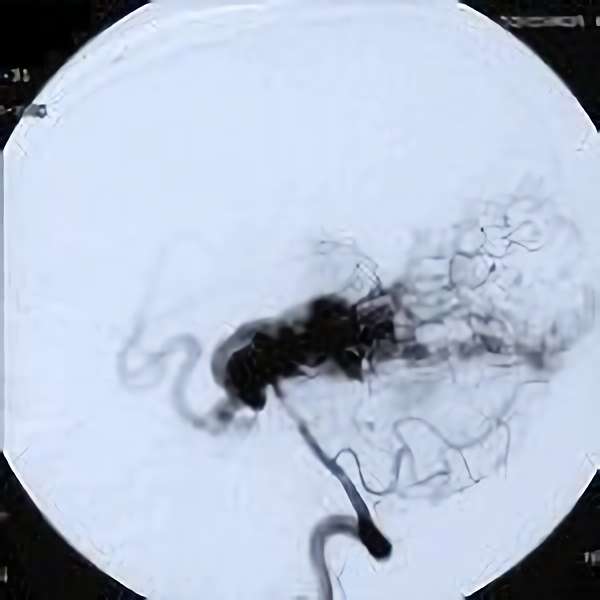

脳血管撮影

手術前

手術後